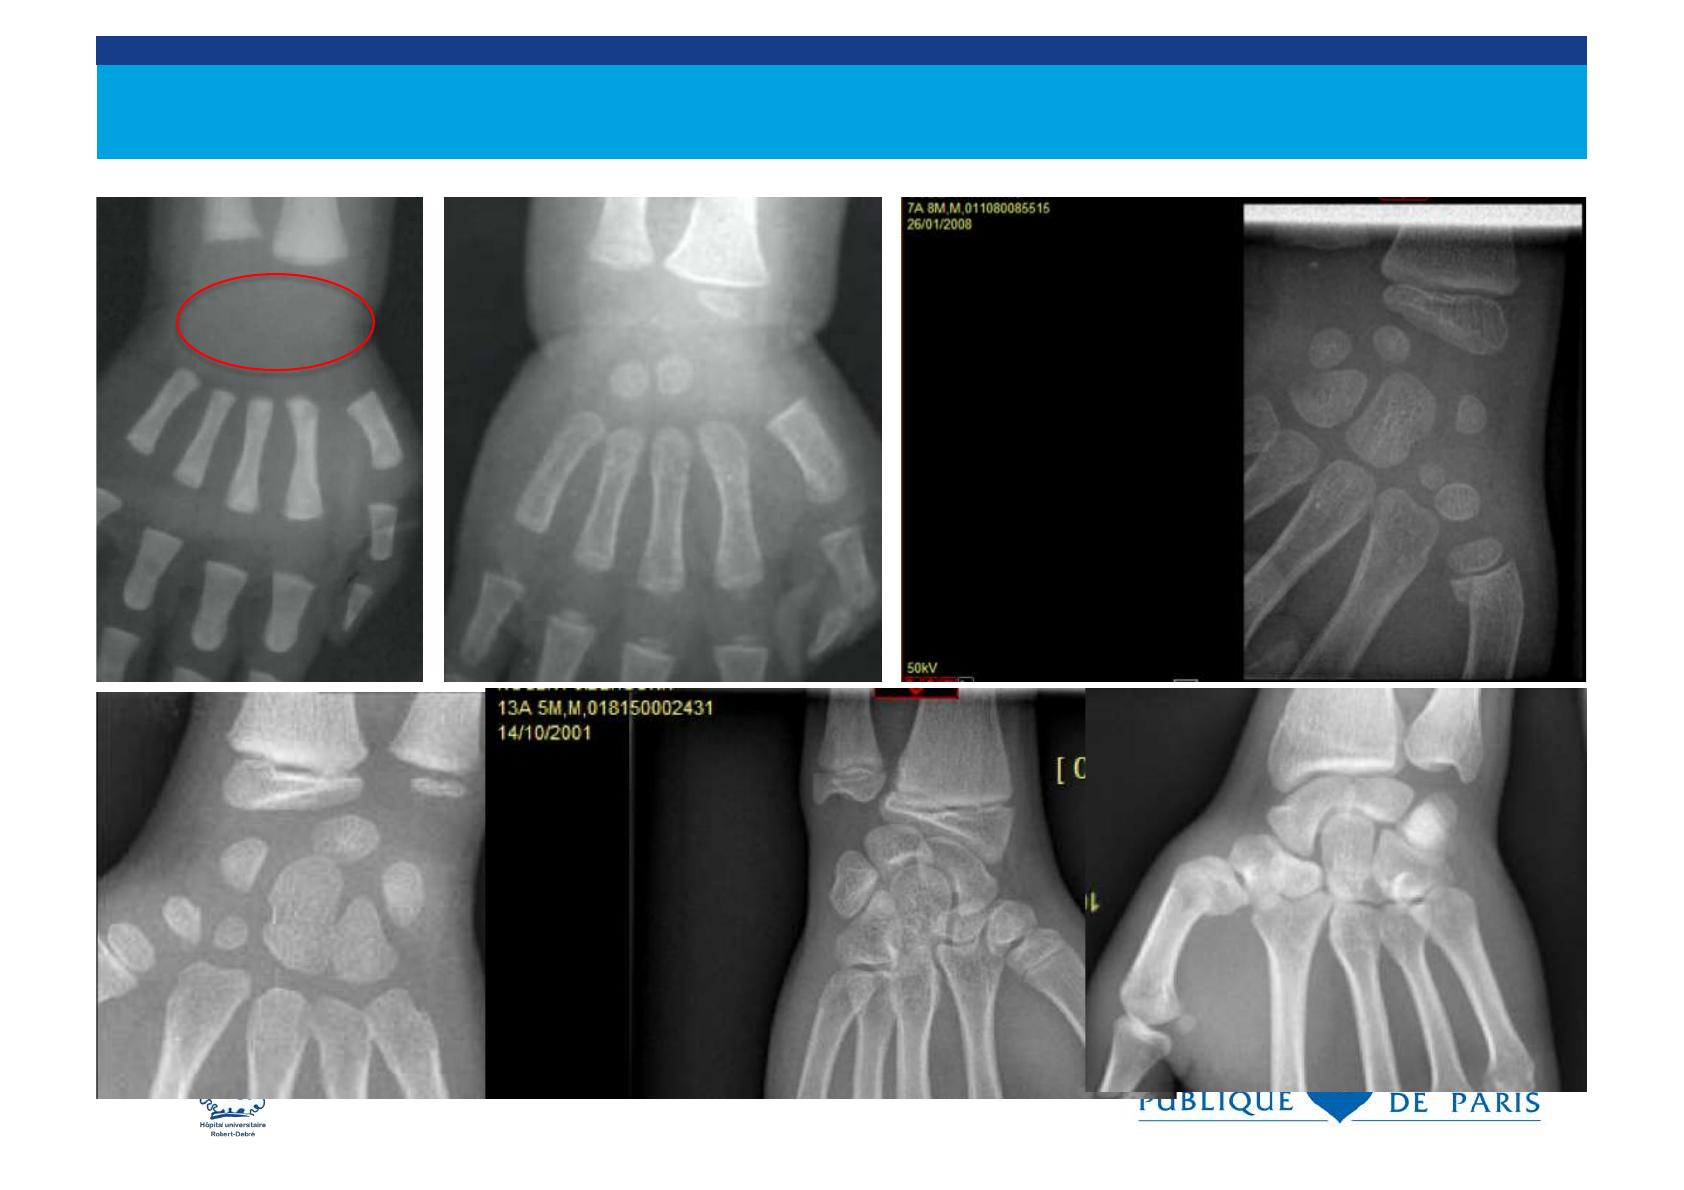

Le cartilage de croissance

. sépare l’ épiphyse de la métaphyse et il est

radiotransparent

. les fractures peuvent traverser le cartilage de

croissance.

. Les traumatismes du cartilage de croissance

déterminent le pronostic des fractures de l’ enfant

métaphyse

épiphyse

cartilage de croissance